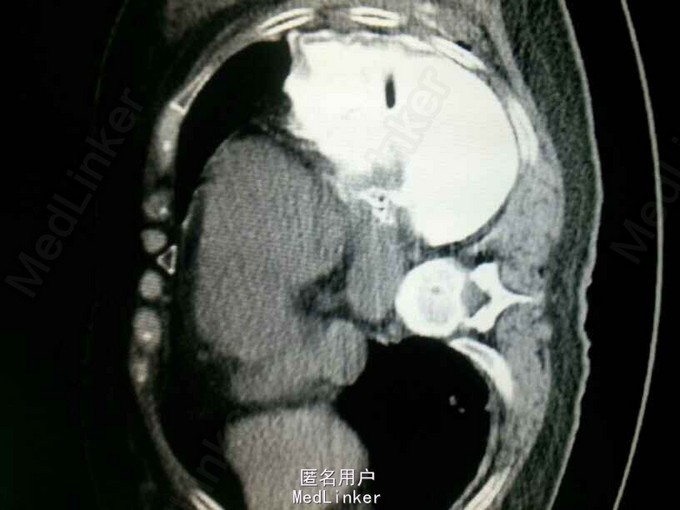

查体:气管居中,左肺呼吸音弱,右肺呼吸音尚可。未闻及湿啰音。胸腔引流管可见褐色浑浊液体引出。 腹部CT肝脾胰未见异常,胆总管扩张。 食管造影:食管下端撕裂,食管胸膜瘘。 胸CT左肺气胸,左侧胸腔内高密度影,考虑造影剂漏入胸腔。左肺实变,右侧少量胸腔积液。

诊断:自发性食管破裂。 治疗:急诊行胸腔闭式引流。后行左剖胸食管破裂修补。术中见胸腔污染严重,见菜叶,消化液等。后纵膈可见较多脓性分泌物,食物残渣,坏死组织。食管裂口处上方可见5cm纵向肌层及粘膜层撕裂口,相应位置处可见纵膈胸膜撕裂口。术后予肠内肠外营养,舒普深,泰能,稳可信,抗感染,术后反复行2次食管造影,仍存在食管破裂口,术后一月行胃镜及食管支架植入术。第二天行进食流质及半流质通畅,平稳出院。